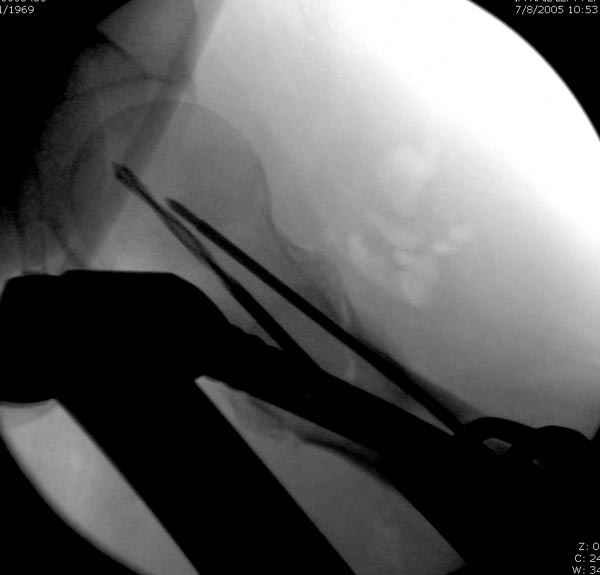

Как раз недавно у меня был примерный случай: больному 36 лет, поступил ночью, травма в результате мотоциклетной аварии, кроме чрезвертельного и спирального перелома левого бедра имеется переломы костей предплечья с этой же стороны. Скелетное вытяжение, а на следующий день больной про оперирован на ортопедическом столе с дистракцией. Чтобы не расколоть чрезвертельный перелом провели временную спицу ближе к переднему кортексу, из малого разреза костодержатель для репозиции, а фиксацию провели антиградным штифтом. Этапы операции на снимках.

Джолдас Кульджанов